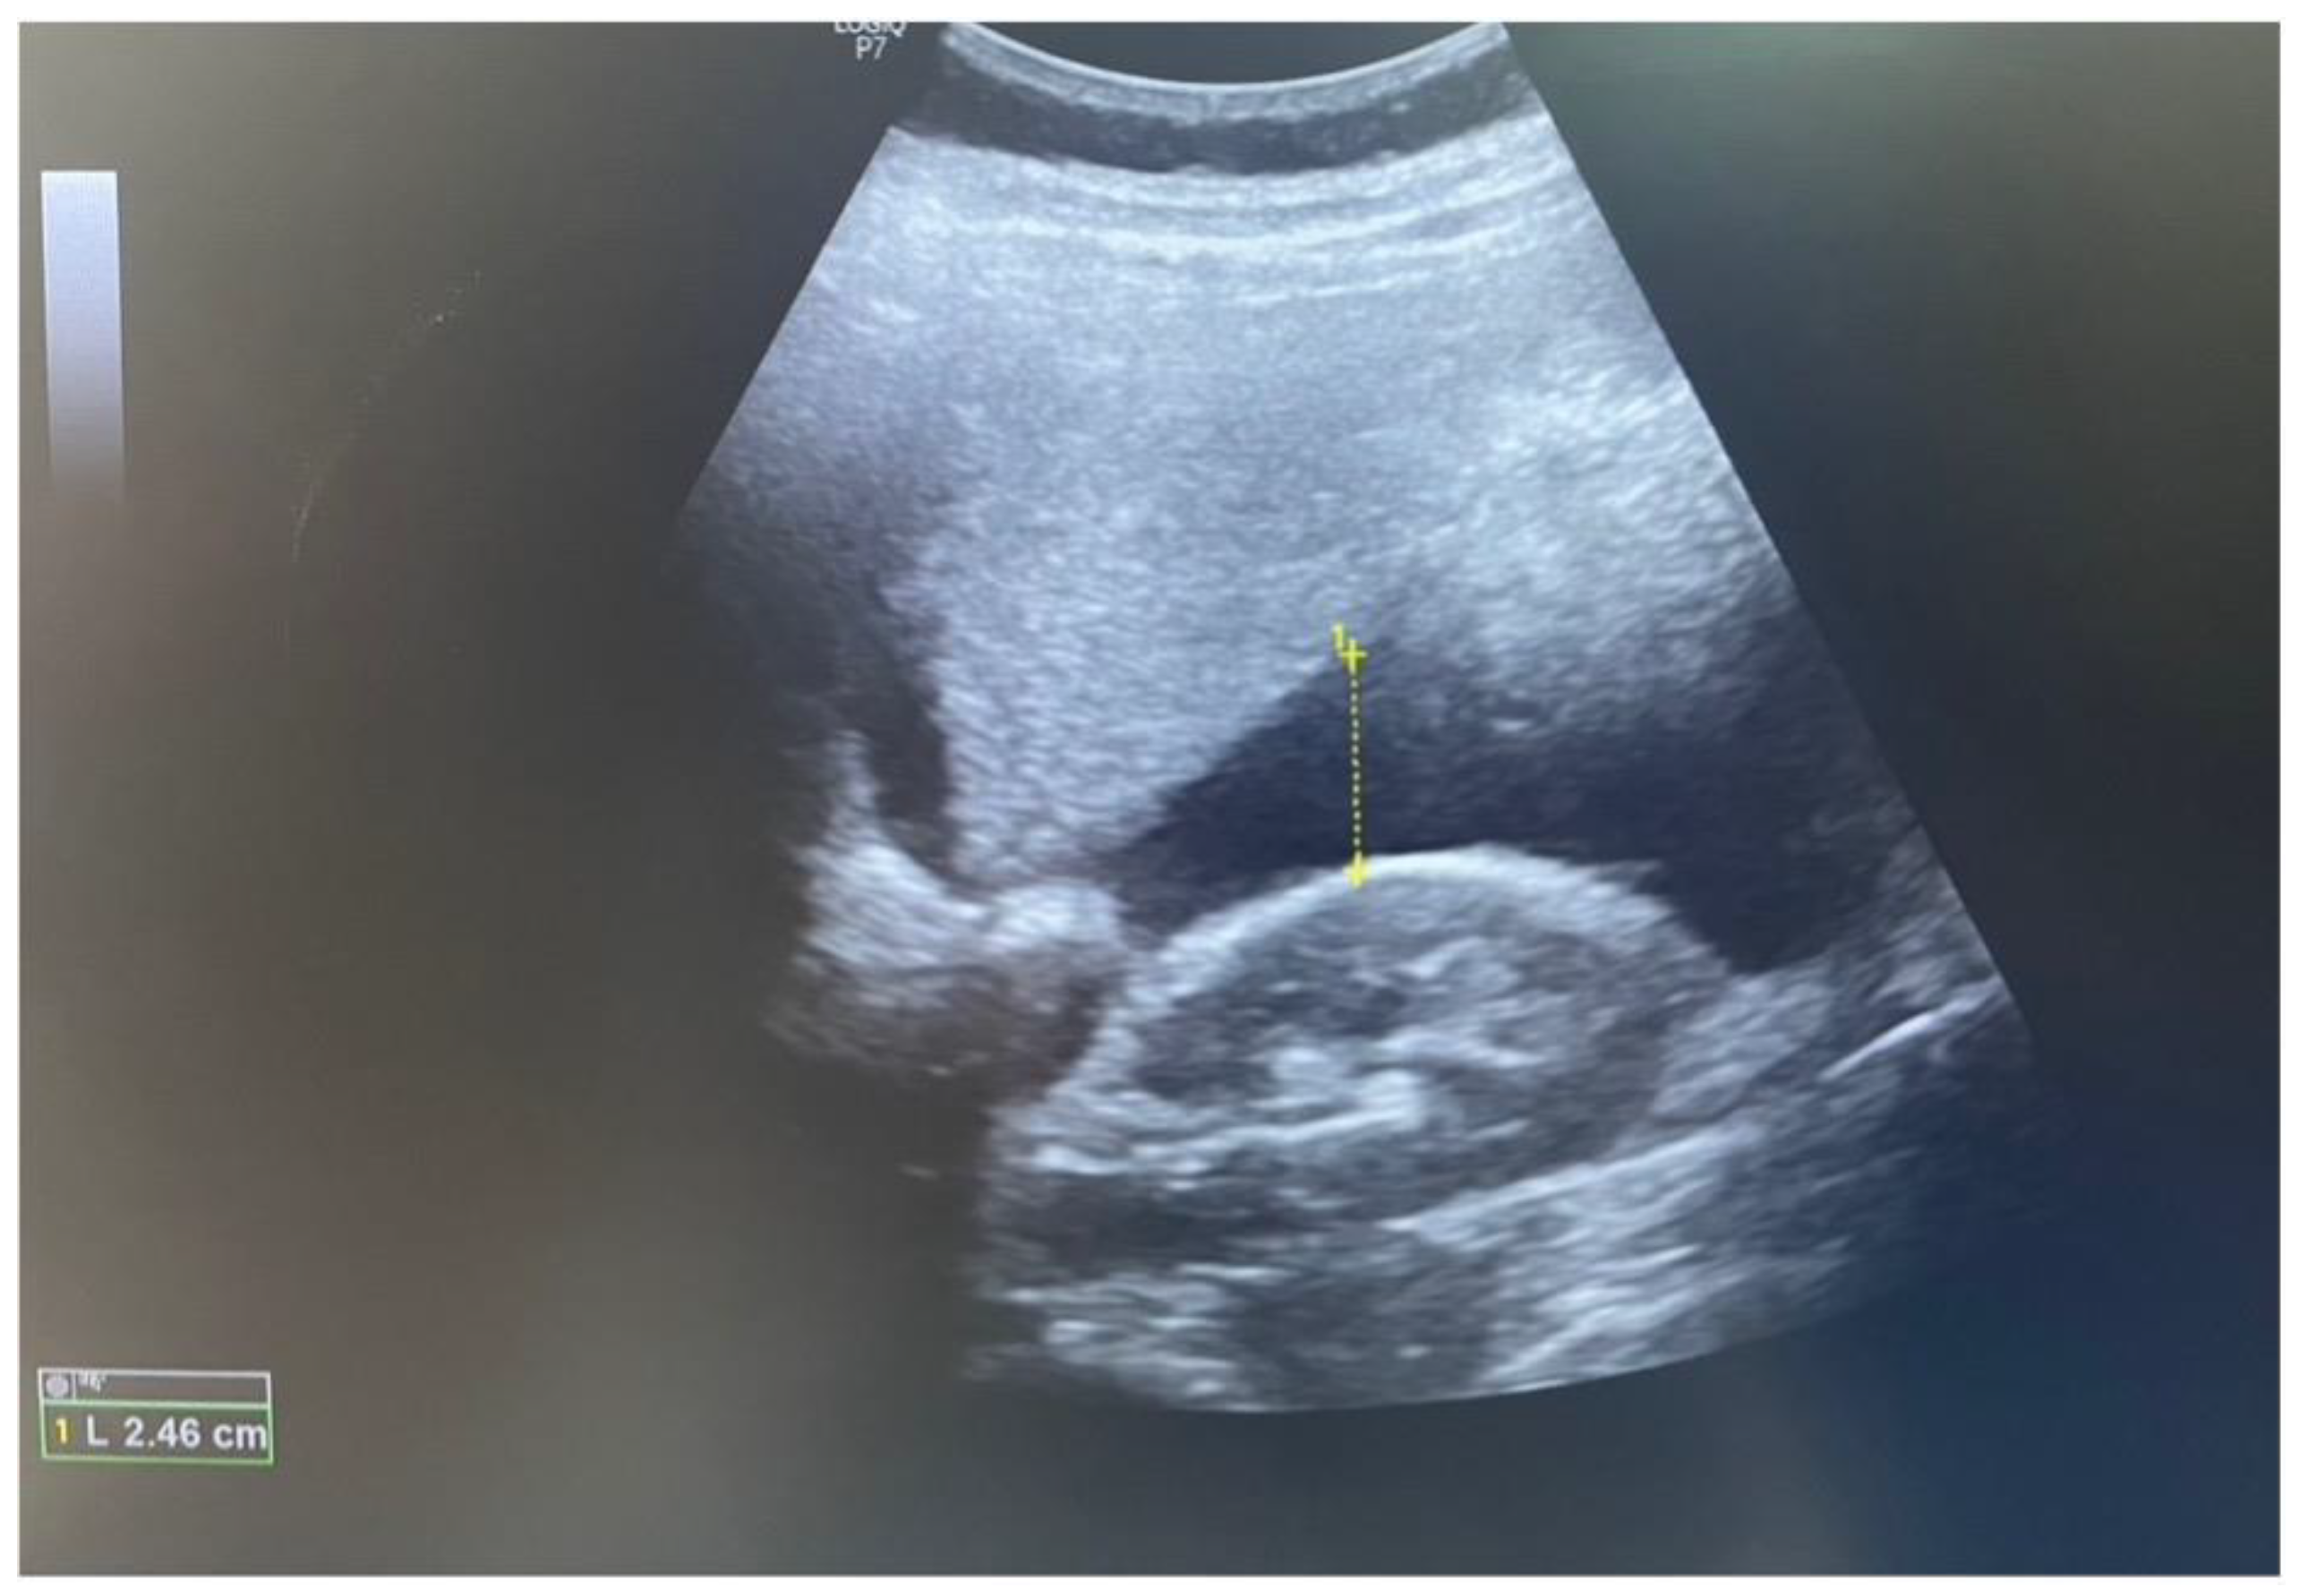

| Our case | lower diffuse abdominal pain and syncope | Intrauterine pregnancy with cardiac activity; free fluid next to the liver and in the pelvis; placental tissue on the anterior uterine wall; no myometrium or serosa at the level of the C-section scar | C-section scar UR | yes |